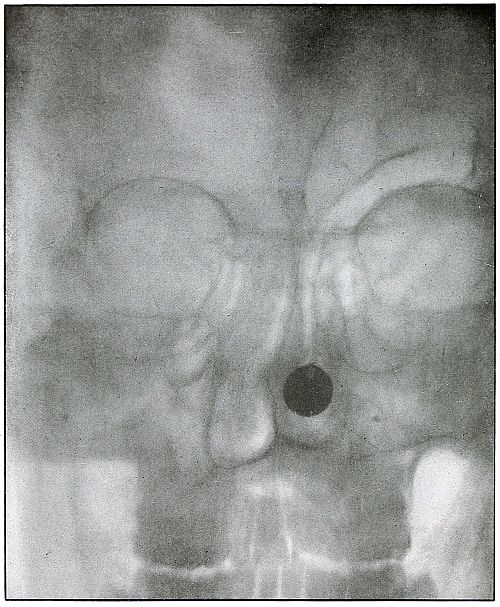

46. Gunshot wound, pelvis 102

115. Gunshot fracture, ilium 240

LOWER EXTREMITY.